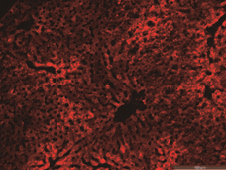

肝脏

心脏

肺部

肌肉